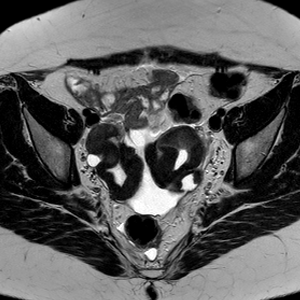

Caso 2 | Abril 2026 | Instituto Oulton

MC: Paciente femenina de 48 años, posmenopausica. Consulta por Metrorragia intermitente de 1 mes de evolución.